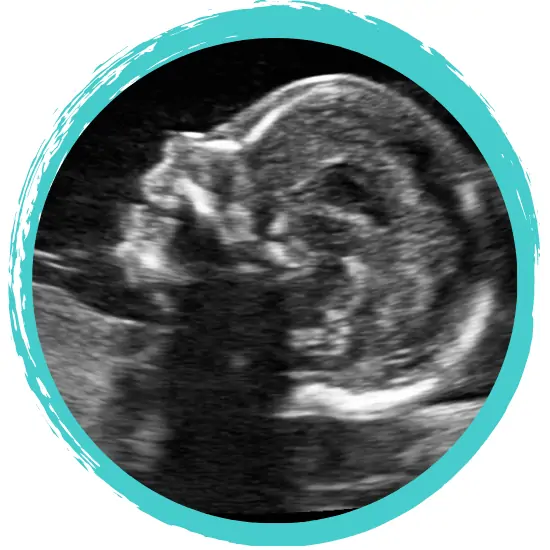

Heading into my 20-week appointment I was so excited to have my 3-year-old and his nanny see this baby. My son finally got to feel the jelly we had talked about, and got to watch this squirming baby I could feel getting stronger. The sonographer pointed out the parts of baby’s body and a healthy heartbeat. The appointment felt longer than previous experiences, but I was consumed watching my son looking at his future brother or sister.

Right at the end, the mention of something wrong. Of the ventricles in baby’s brain being enlarged and that doctors would need to review. I thought nothing of it. I assumed the brain was just growing ahead of schedule. The sonographer invited me to take a video and sent us on our way. Being ever positive, I was sure this was nothing to worry about.

We finally got called into the ultrasound room. The memory feels dimly lit, like some kind of staged show. Again, a sonographer showed us what looked like a perfect 20-week ultrasound, tracking in all the right ways. Healthy heartbeat. Strong kicks fighting the sonographer. This was different though. Anxiety. Fear. Doubt. The sonographer asked what did we know so far. “Only what we found on Google.” It was explained that while Google will tell you that Ventriculomegaly is diagnosed as mild to severe, anything close to borderline normal is concerning. A condition that occurs in approximately one in 1,000 infants.